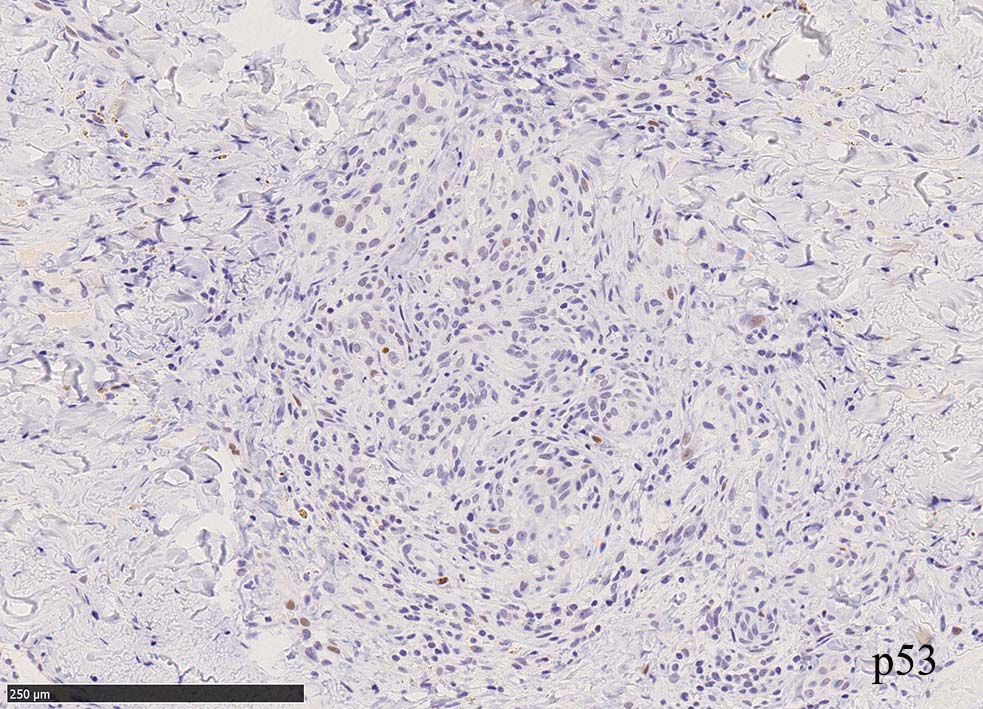

免疫染色, 分子病理学的検査

増生細胞はCD31, CD34, Factor Ⅷ, D2-40などが陽性を示す.

HHV-8の潜伏期関連抗原(HHV-8 Latency-associated nuclear antigen: HHV-8 LANA)が市販されており, 核が点状に染色される陽性所見がKaposi肉腫の確定診断に必須となっている.